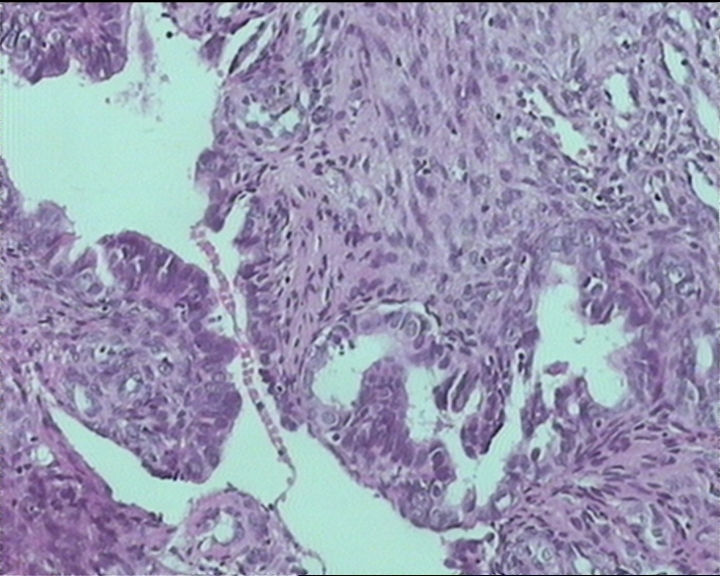

54岁女性,临床“宫颈息肉”送检;巨检:组织一块1。5*1CM,灰红。

细胞及腺体均有异形,图6、11、16象有纤维间质反应,考虑高级别上皮内瘤变/原位癌,腺癌不能除外。

输卵管粘膜化生

It is benign. Benign endocervical polyp with tubal metaplasia.

Sternberg病理学上诊断宫颈原位腺癌的标准是腺体的上皮去粘液分化,呈乳头状或筛网状增生,核分裂易见,这例显然达不到此标准。此例还是归入到腺上皮不典型增生为好。